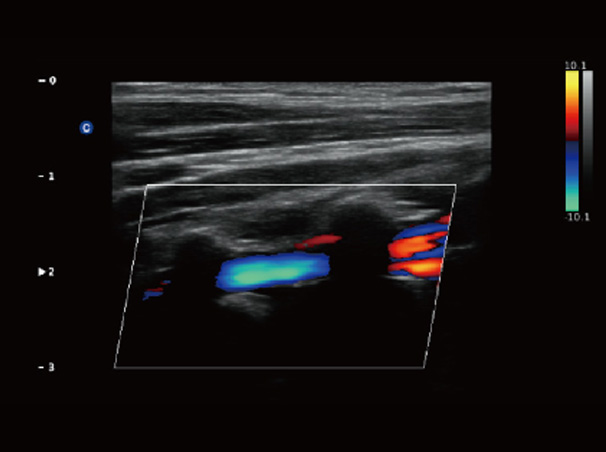

Chison Qbit 3 Color Doppler Digital Ultrasound Machine

Chison Qbit 3 A Slim Console Color Doppler System, Offers Ideal Patient Care With Its Easy Mobility, Smart Features, Significant Performance And Streamlined Workflow, To Strengthen The Clinical Confidence And Speed The Diagnostic Decision.

QBit 3 Slim.Smart.Significant.Streamlined

Chison Qbit 3 Ultrasound Machine

Chison QBit-3 Ultrasound Machine System, Offers Ideal Patient Care With Its Easy Mobility, Smart Features, Significant Performance And Streamlined Workflow, To Strengthen The Clinical Confidence And Speed The Diagnostic Decision.